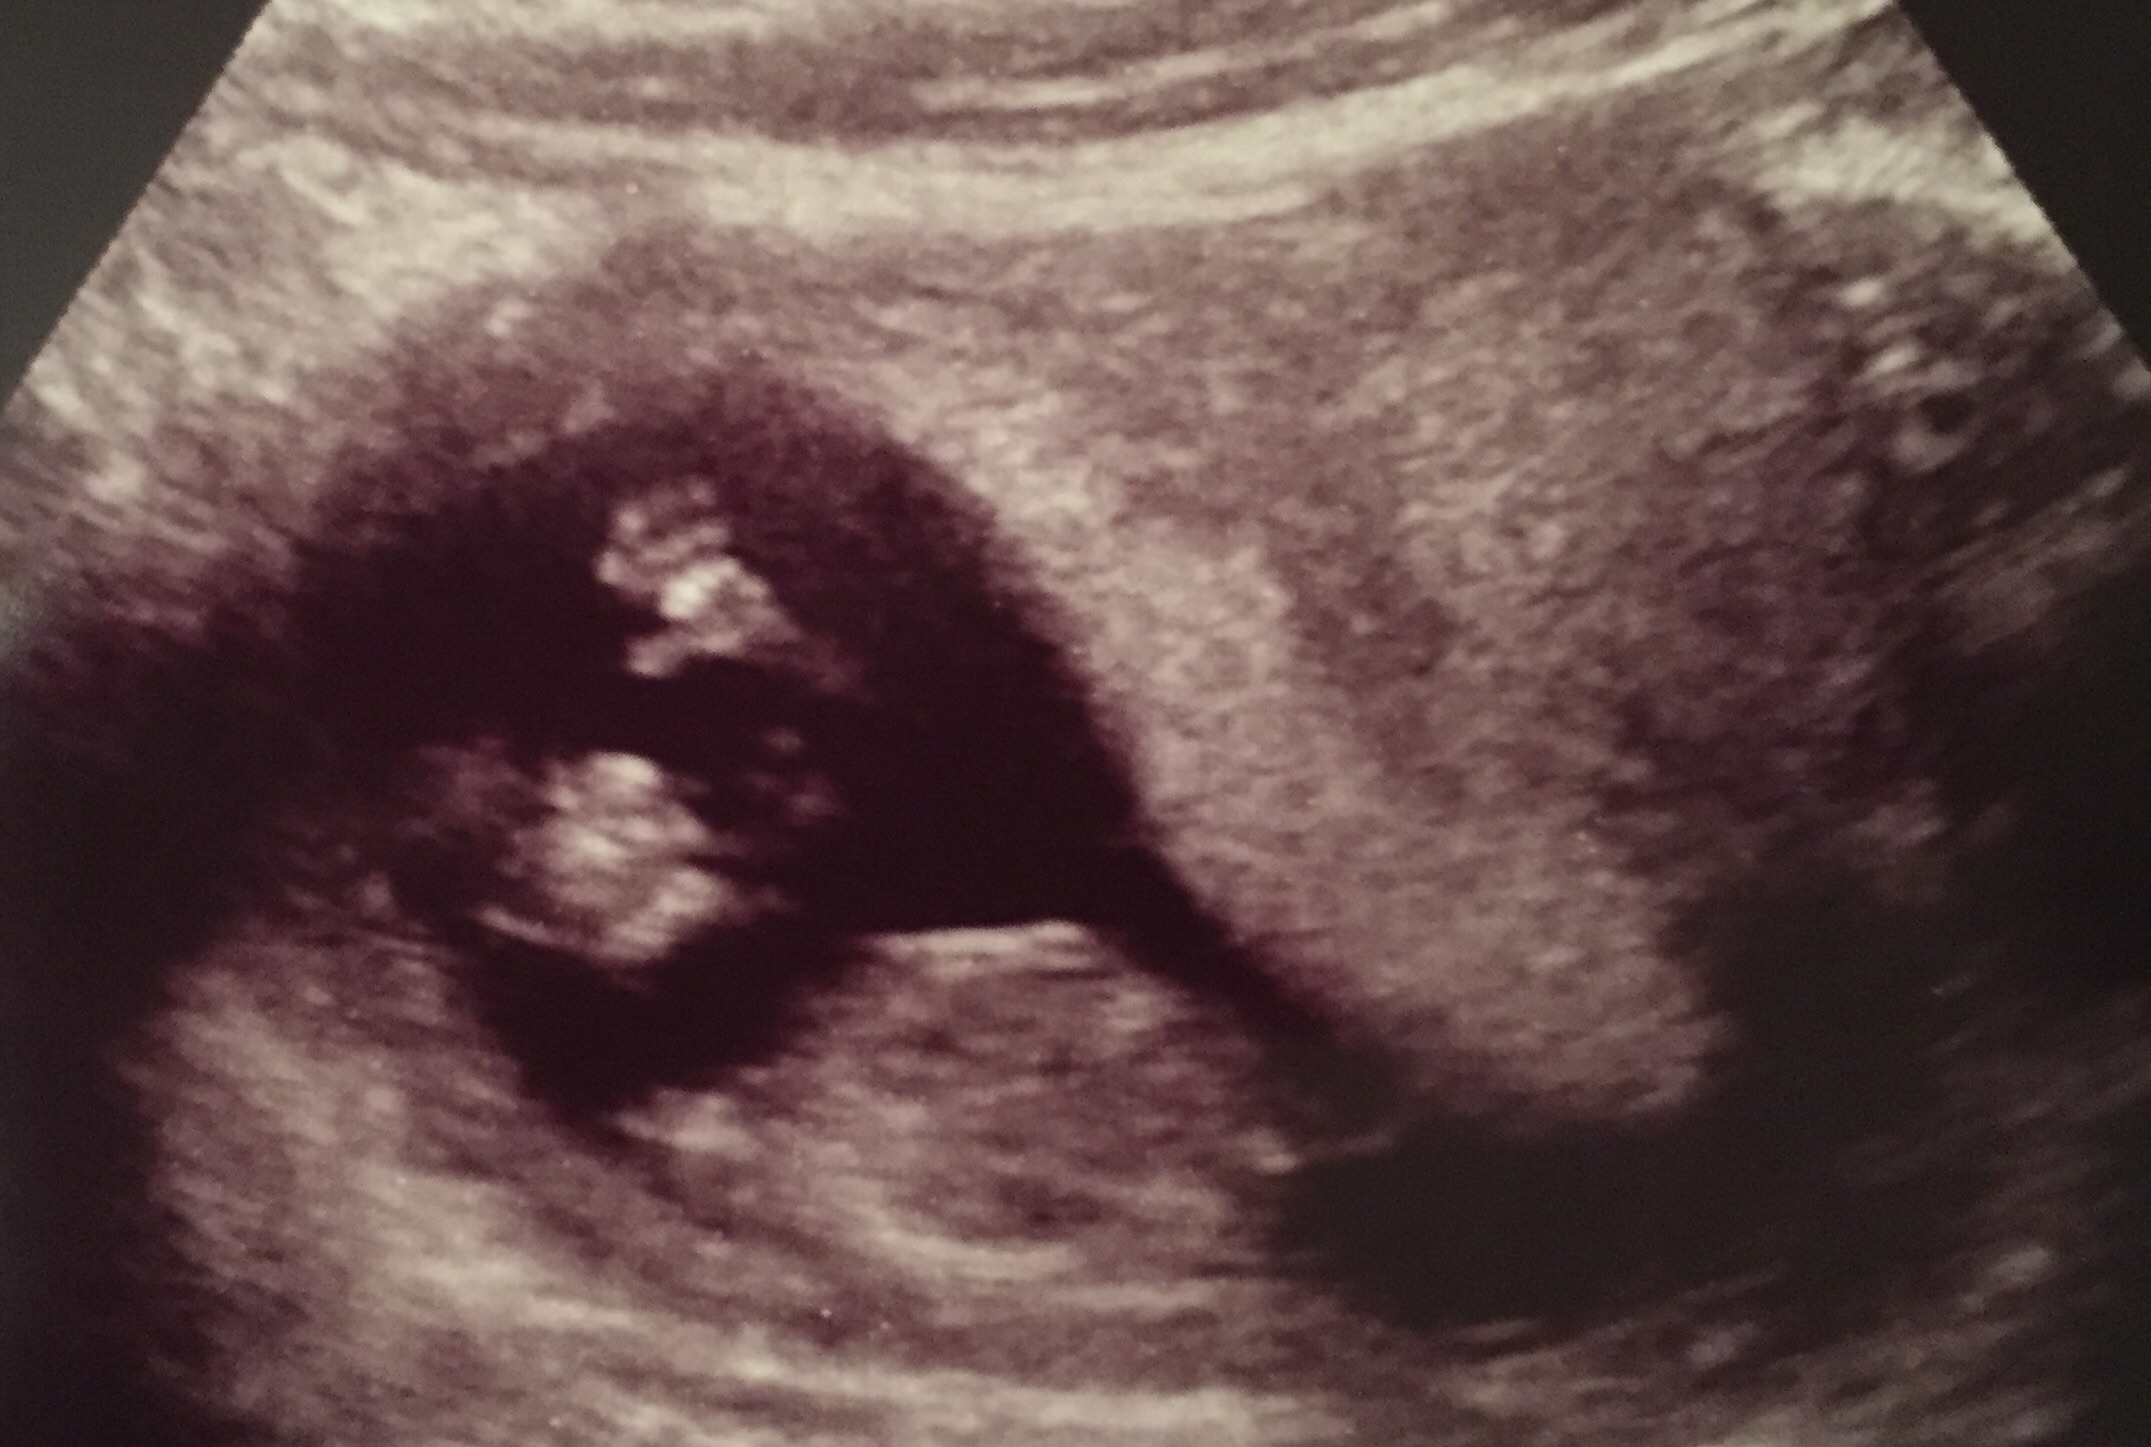

I just cleared off all my phone pictures a couple months ago to make room for lots of baby pictures come August! This pic is from when I was trying on dresses for my maternity photo shoot to send to my BFF to get her opinion.

#3 born August 2015 #4!!!!!!! due June 2017

#4!!!!!!! due June 2017